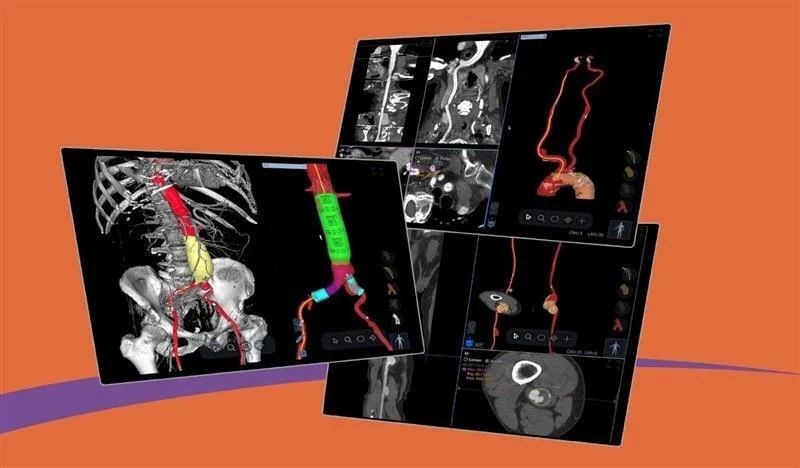

New solution brings advanced vascular analysis into the cvi42 cardiovascular imaging ecosystem. Highlights Circle Cardiovascular Imaging (Circle CVI) has expanded its cvi42 platform to include advanced Vascular CT analysis, integrating Astute Imaging’s AI-driven vascular analysis technology. This enhancement enables comprehensive cardiovascular workflows, allowing clinicians to perform cardiac, vascular, and structural heart analysis within a single, unified platform. This integration supports greater efficiency and collaboration across cardiology, radiology, and vascular surgery teams, advancing the use of quantitative, AI-enabled imaging for diagnosis, procedural planning, and post-treatment management Calgary, AB — March 18, 2026 — Circle Cardiovascular Imaging (Circle CVI) today announced the expansion of its cvi42 cardiovascular imaging platform to include advanced Vascular CT analysis, further extending the platform’s capabilities across cardiovascular imaging workflows. The new solution is enabled through a collaboration with Astute Imaging, whose AI-driven vascular analysis technology has been integrated into the cvi42 ecosystem. The addition of Vascular CT capabilities allows clinicians to analyze complex vascular anatomy for diagnosis, endovascular procedure planning, and post-treatment surveillance, all within the same platform used for cardiac imaging and structural heart planning. Advancing Quantitative Cardiovascular Imaging As healthcare systems increasingly adopt quantitative imaging and AI-enabled workflows, clinicians are seeking integrated platforms that can support the full continuum of cardiovascular care — from diagnosis to procedural planning and long-term disease management. The new Vascular CT capabilities extend the scope of cvi42 beyond cardiac imaging, enabling automated vascular analysis within the same environment trusted by cardiovascular teams worldwide. The technology powering these capabilities was developed by Astute Imaging, whose advanced algorithms support automated segmentation, quantification, and visualization of vascular structures. “Fragmented imaging workflows can slow collaboration and decision making between cardiovascular teams,” said Dr. Kevin Steel, Chief Medical Officer, Circle CVI. “By bringing vascular CT analysis into the cvi42 ecosystem, clinicians can work from the same platform across cardiac and vascular cases, helping improve efficiency and coordination of care.” Cardiac and vascular analysis within a unified workflow helps multidisciplinary cardiovascular teams collaborate more effectively across cardiology, radiology, and vascular surgery. ABOUT CIRCLE CARDIOVASCULAR IMAGING Circle Cardiovascular Imaging Inc. (Circle CVI) is a Canadian-based company founded in 2007 with a mission to develop innovative software solutions that enhance cardiovascular and cerebrovascular imaging analysis and ultimately improve patient care. Circle’s flagship platform, cvi42 , delivers best-in-class image reading and reporting tools for quantitative and qualitative assessment of cardiac MR, cardiac CT, vascular CT, and neuro CT . At the core of Circle’s work is a relentless commitment to empowering healthcare providers with advanced, intuitive tools that lead to better healthcare outcomes. This passion for innovation, rooted in both medicine and technology, drives Circle’s global impact and fuels a culture of excellence. Today, millions of medical imaging exams each year, across 1,700+ hospitals in over 90 countries, are interpreted using Circle’s cvi42 platform. For more information, please visit www.circlecvi.com or contact: marketing@circlecvi.com About Astute Imaging Astute Imaging Inc. is a U.S.-based company founded in 2022 with a mission to become a best-in-class provider of AI-enabled vascular imaging and care management software for healthcare providers and MedTech companies. Astute Imaging delivers a fully automated, AI-enabled workflow supporting diagnostics, surgical planning, and longitudinal patient follow-up. The platform covers all major vascular anatomies, including the aorta, carotid arteries, and peripheral vasculature. In addition, Astute Imaging provides AI-enabled virtual device simulation, allowing surgeons to visualize and automatically identify the most appropriate device for a patient’s anatomy, enabling highly personalized procedural planning and care management. Astute Imaging’s technology is also used by medical device companies for regulatory and research applications, including core lab services and R&D support. For media inquiries, please contact: marketing@astuteimaging.com